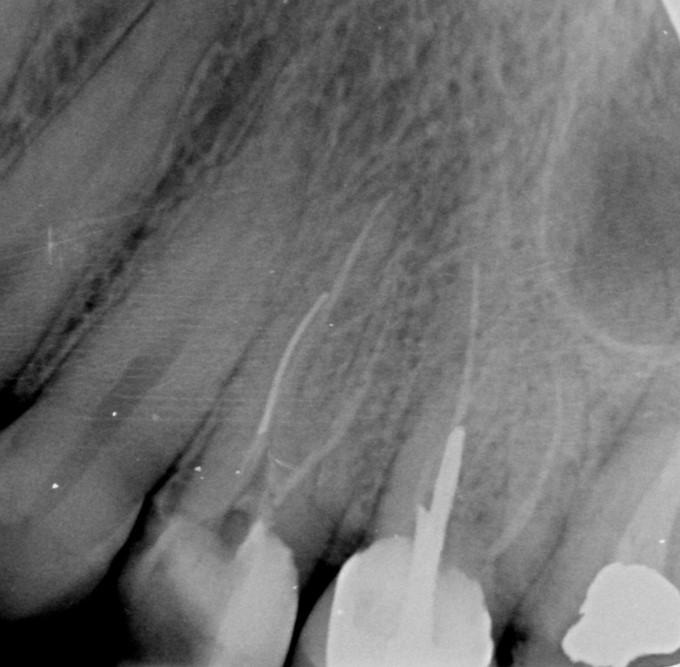

Long and calcified maxillary first molar

شکایت اصلی بیمار: درد پس از پانسمان دندان سابقه درمان دندانپزشکی: دندان مولر اول ماگزیلا (3#) دو هفته قبل تحت درمان ترمیمی قرار گرفته ولی با توجه به وسعت پوسیدگی، جهت درمان ریشه ارجاع شده است.